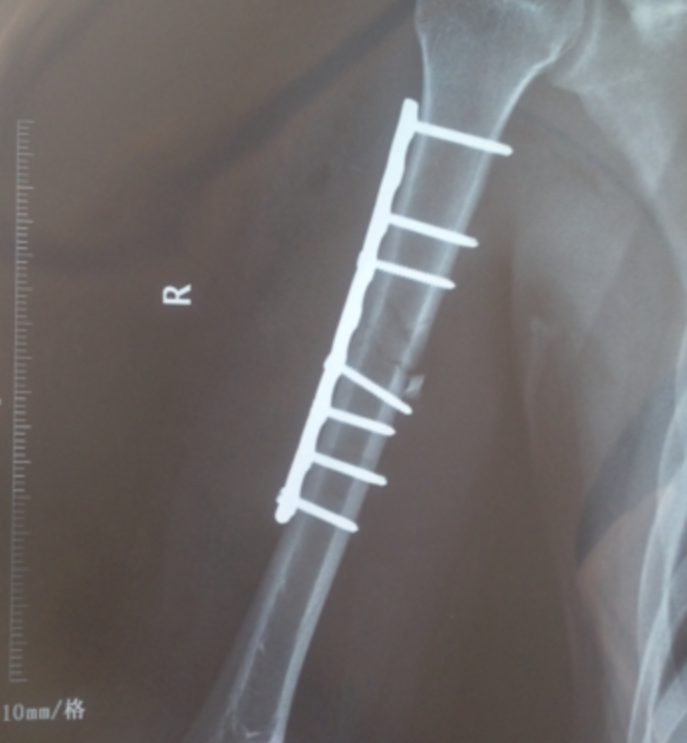

“他早年出过一场车祸,当时整条右胳膊都被车给压了,然后去了医院以后确诊是粉碎性骨折,就做了那个钢板的手术,但是因为家里没钱给我爸爸取钢板、我爸爸也没打算取,所以那块钢板一直到现在都还在他的胳膊里。”杨堋无法控制住情绪,哽咽了起来。